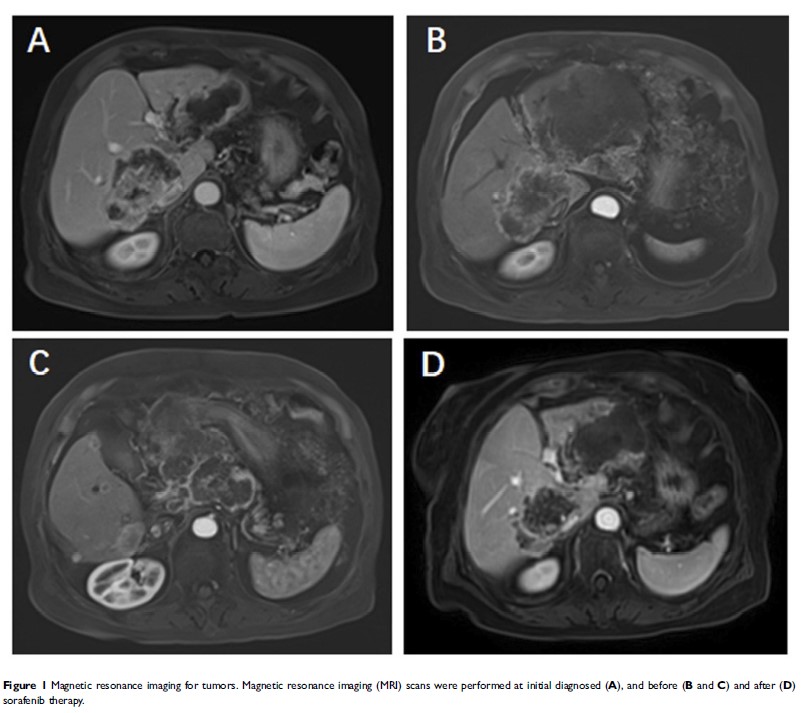

Case Report

FGFR2-BICC1 : 在胆管癌中的 FGFR2 亚型致癌融合变体和对索拉非尼的反应

- 作者:Xihui Ying, Jianfei Tu, Wenxian Wang, Xingliang Li, Chunwei Xu, Jiansong Ji

- 期刊:OncoTargets and Therapy